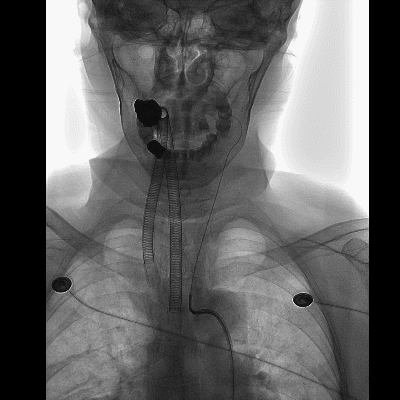

全麻下,右侧股动脉置入8F血管鞘,在泥鳅导丝及5F椎动脉型造影导管引导下将6F NeuronMax长鞘送至左侧颈内动脉起始,撤出造影导管。

6F 115cm SKATHI远端通路导管与6F NeuronMax长鞘同轴,在泥鳅导丝引导下将SKATHI远端通路导管送至左侧颈内动脉海绵窦段。

山高路远,道路迂曲

SKATHI轻松通过